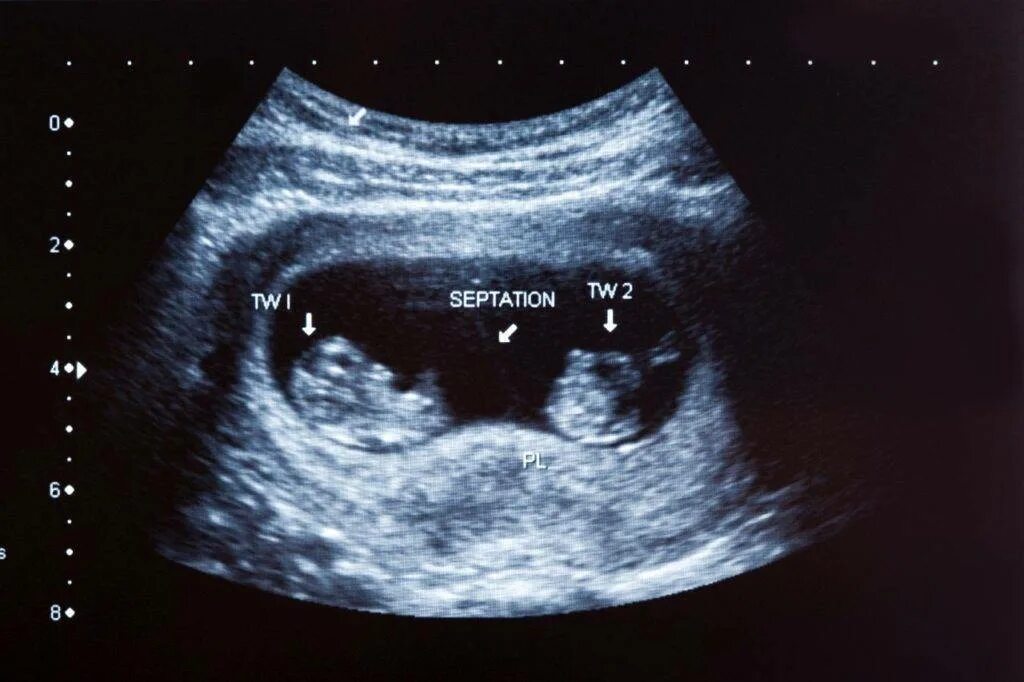

На каком сроке можно увидеть двойню